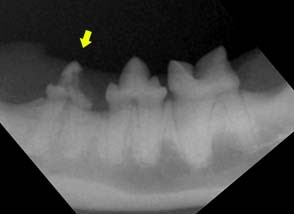

Specie nei gatto i problemi dei denti sono nascosti al disotto della gengiva dove si evidenziano pulpiti ed erosioni delle radici per esaminare bene questo denti si deve valutare bene il colletto dentario (limite tra dente e gengiva ) dove spesso è presente, sanguinamento e proliferazione di tessuto con presenza di di fori o cavità .

Questi denti devono essere asportati con urgenza altrimenti l’infezione progredisce attraverso i seni .

Spesso infatti sfuggono alla visita tante lesioni dentali che se trascurate possono evolvere in pulpiti (infiammazioni del nervo sito nella radice dentaria), paradontiti , forme patologiche che spesso degenerano in neoplasie.

La bocca ad un primo superficiale esame visivo, puo sembrare apparentemente sana, perchè il dente si presenta integro esternamente, ma può non esserlo la radice nascosta sotto la gengiva , infatti non di rado, capita che andando a sondare con specilli o radiografie si notano erosioni delle radici e zone ipersensibili e doloranti che impediscono all’animale di masticare bene ingoiando il cibo intero.